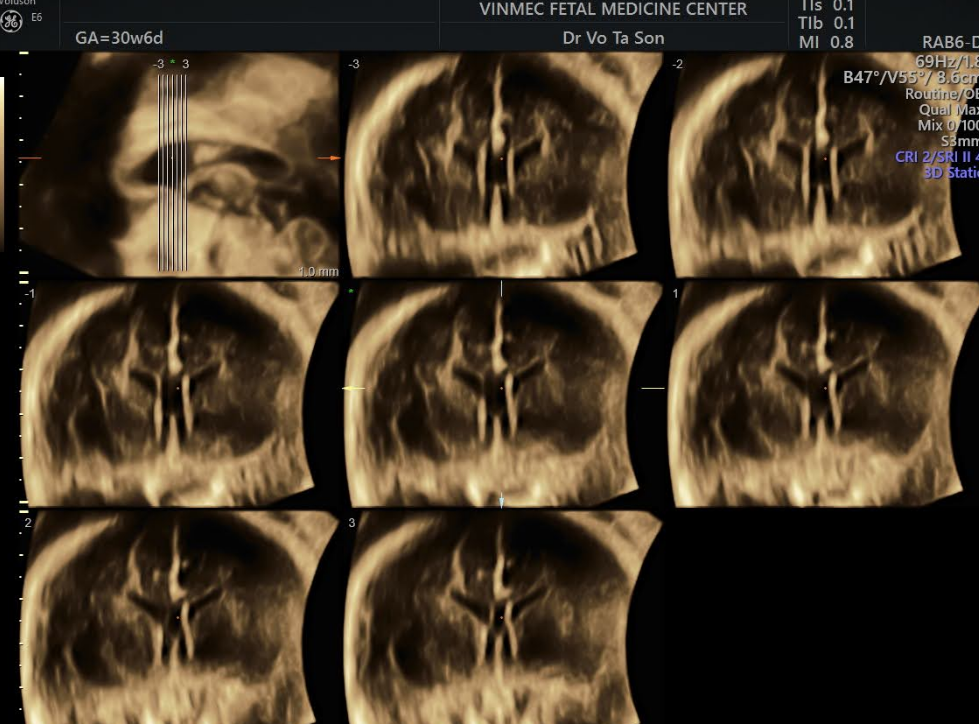

- Việc sử dụng siêu âm thai nhi ngày càng tăng, có thể phát hiện sự vắng mặt của vách ngăn niêm mạc và tăng kích thước tâm thất, tiếp theo là MRI thai nhi, thêm vào việc phát hiện sớm dị tật này.